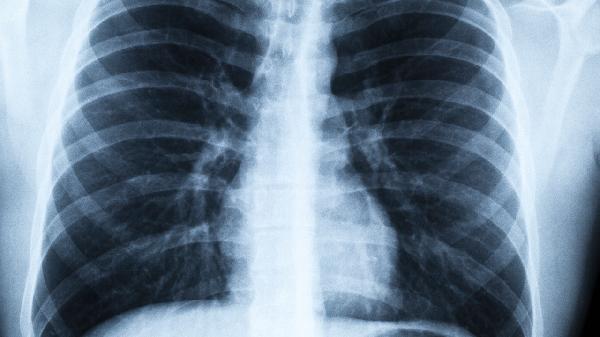

1、低剂量CT最可靠

相比胸片,CT能发现小于1厘米的微小结节,检出率提高20%以上。40岁以上高危人群应每年检查。